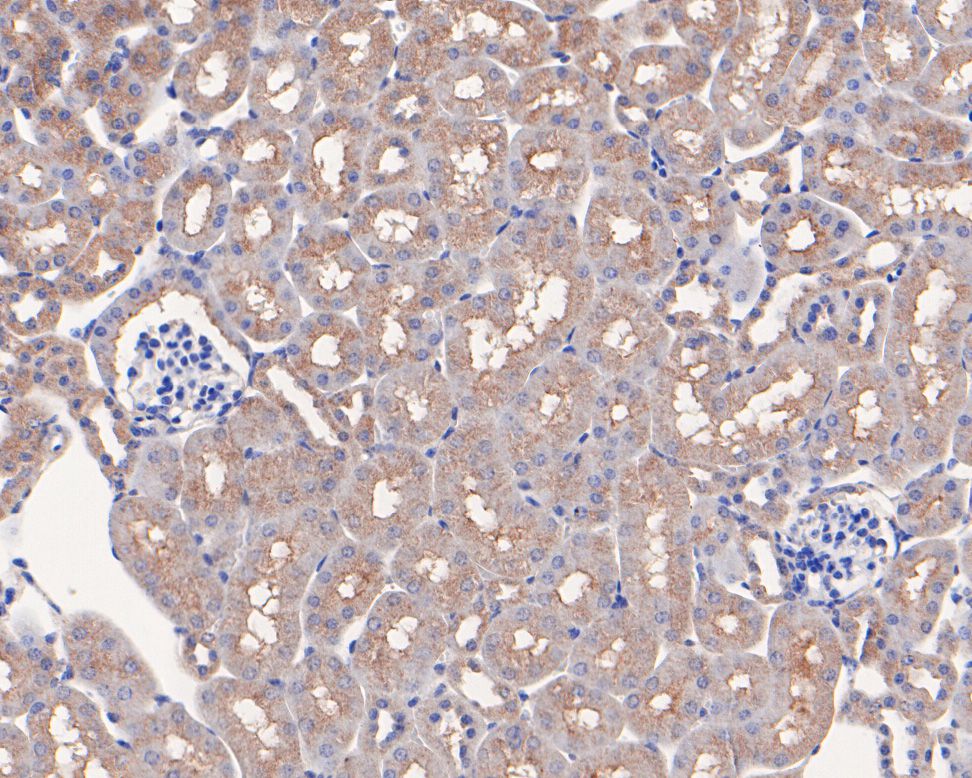

Immunohistochemical analysis of paraffin-embedded human kidney tissue using anti-MCL1 antibody. The section was pre-treated using heat mediated antigen retrieval with Tris-EDTA buffer (pH 8.0-8.4) for 20 minutes.The tissues were blocked in 5% BSA for 30 minutes at room temperature, washed with ddH2O and PBS, and then probed with the primary antibody (ET1606-14, 1/50) for 30 minutes at room temperature. The detection was performed using an HRP conjugated compact polymer system. DAB was used as the chromogen. Tissues were counterstained with hematoxylin and mounted with DPX.